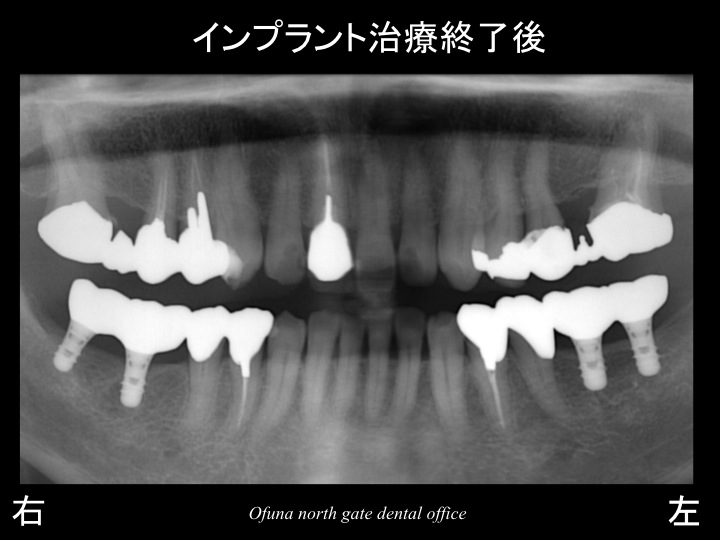

以下がインプラント治療が終了した直後です。

治療期間は、約3ヶ月です。

インプラントを埋入(手術後)後、骨とインプラントが結合(くっつく)まで約2〜3ヶ月かかるためです。